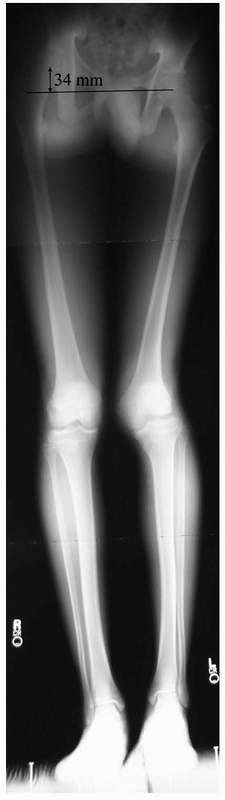

overdistraction and are characterized by their direction and magnitude.

They are measured from joint center to joint center in centimeters on

plain radiographs and compared to the contralateral normal extremity,

using an x-ray marker to correct for magnification (Fig. 26-9).91

![]() |

FIGURE 26-9 Bilateral standing 51-inch AP alignment radiograph reveals a 34-mm leg length inequality.